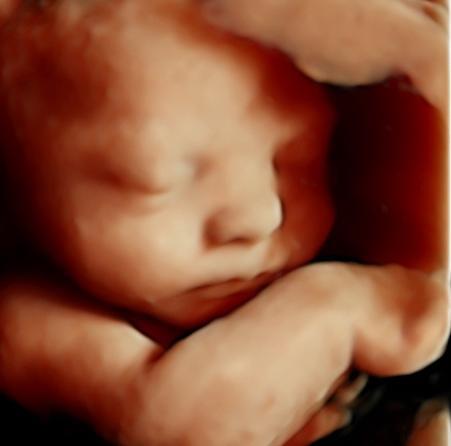

Com a inovação da medicina diagnóstica a ultrassonografia em 4D consegue avaliar a morfologia fetal em três dimensões em tempo real. As imagens tridimensionais permitem ver estruturas como as mãos, pés, orelhas, nariz, boca e ainda a fisionomia do bebê.

A Imax possui o mais novo aparelho de ultrassonografia obstétrica o Voluson E8 Expert HD Live, o qual permite um diagnóstico mais confiável através da visualização de imagens fetais com alto realismo anatômico.